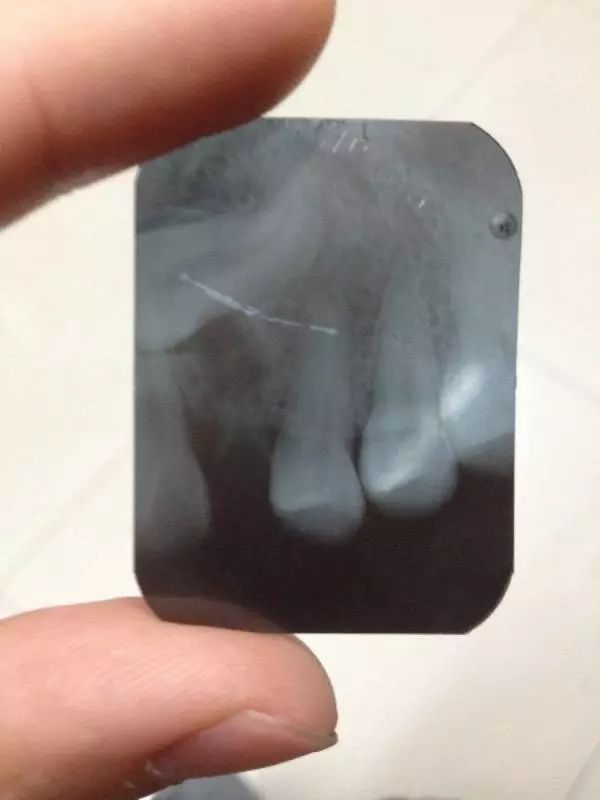

后来,张女士因为陪同朋友到暨南大学附属第一医院穗华口腔医院找赖仁发教授做口腔治疗,她向赖教授询问自己的发烧以及口腔问题。在经过仔细的囗腔检查后,赖仁发教授建议张女士拔除左下的几颗残牙根。张女士接受了这个治疗方案,赖仁发教授釆用微创无痛术为她拔掉了几颗残牙根。

几天后,张女士前来复诊,高兴地告诉医务人员:她以前每天都定时出现的低烧现象,现在再也没有出现了,身体不适的症状也消除了。拔除残牙为何就能解决患者长期发烧的问题呢?对此,口腔医学博士生导师赖仁发教授指出,患者长期发低烧,可能与她多颗龋齿的残牙有关。因为龋齿是一种由口腔中多种因素导致的牙病,表现为无机质脱矿和有机质分解,随病程发展而从色泽改变到形成实质性病损的演变过程。龋齿是细菌性疾病,因此它可以继发牙髓炎和根尖周炎,甚至能引起牙槽骨和颌骨炎症。龋齿的继发感染可以形成病灶,残牙成了细菌储藏室,容易引起口腔疾病的反复发作,还可以形成全身其他疾病。